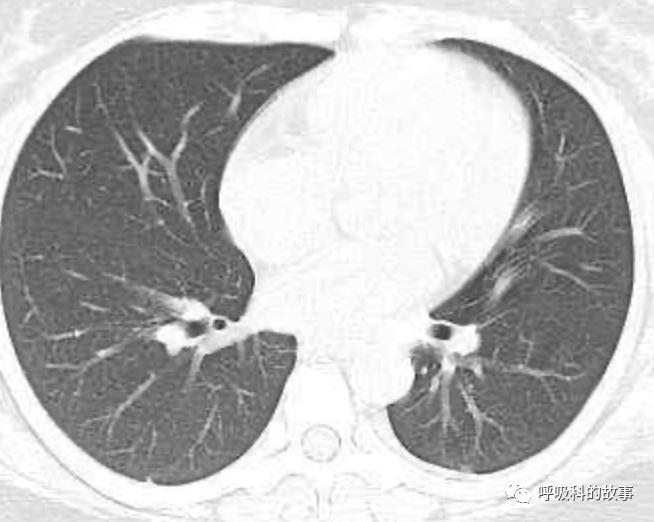

患者发热后行胸部CT检查(6月21日,住院第13天),可见两下肺有条片影,当时考虑是肺炎引起的发热。

可是在6月26日(往院第18天)仍持续发热的情况下复查肺部CT,肺部病灶已明显吸收了。那么患者发热的原因到底是什么呢?为什么患者高热的情况下血白细胞不升反降,C反应蛋白也没有明显增高?这个时候消化科医生也迷茫了,这可怎么办?于是请感染科和呼吸科医生一起会诊,共商计策。